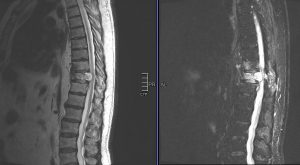

Διενεργήθη αποσυμπίεση του νωτιαίου μυελού μέσω πεταλεκτομίας και αφαίρεσης του ενδοκαναλικού τμήματος του όγκου και στη συνέχεια διαδερμική σπονδυλοδεσία με έγχυση οστικού τσιμέντου στα σπονδυλικά σώματα Θ9-Θ11

O ασθενής παρουσίασε άμεση βελτίωση του άλγους του και βελτίωση της στάσης σώματος κατά τη βάδιση. Εξήλθε την 2η μετεγχειρητική ημέρα.